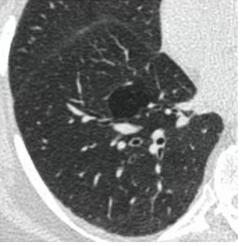

2. Наличие клинических проявлений, указанных в п. 1, в сочетании с характерными изменениями в легких по данным компьютерной томографии (КТ) (см. Приложение 1 настоящих рекомендаций) вне зависимости от результатов однократного лабораторного исследования на наличие РНК SARS-CoV-2 и эпидемиологического анамнеза.

- Изменения при КТ (рентгенографии), типичные для вирусного поражения (объем поражения минимальный или средний; КТ 1-2)

КТ имеет высокую чувствительность в выявлении изменений в легких, характерных для COVID-19. Применение КТ целесообразно для первичной оценки состояния ОГК у пациентов с тяжелыми прогрессирующими формами заболевания, а также для дифференциальной диагностики выявленных изменений и оценки динамики процесса. КТ позволяет выявить характерные изменения в легких у пациентов с COVID-19 еще до появления положительных лабораторных тестов на инфекцию с помощью МАНК. В то же время, КТ выявляет изменения легких у значительного числа пациентов с бессимптомной и легкой формами заболевания, которым не требуется госпитализация. Результаты КТ в этих случаях не влияют на тактику лечения и прогноз заболевания при наличии лабораторного подтверждения COVID-19. Поэтому массовое применение КТ для скрининга асимптомных и легких форм болезни не рекомендуется.

3. Применение лучевых методов у пациентов с симптомами ОРВИ легкой степени тяжести и стабильном состоянии пациента, возможно только по конкретным клиническим показаниям, в том числе при наличии факторов риска, при условии достаточных технических и организационных возможностей. Методом выбора в этом случае является КТ легких по стандартному протоколу без внутривенного контрастирования или РГ при ограниченной доступности КТ. Использование УЗИ в этих случаях нецелесообразно.